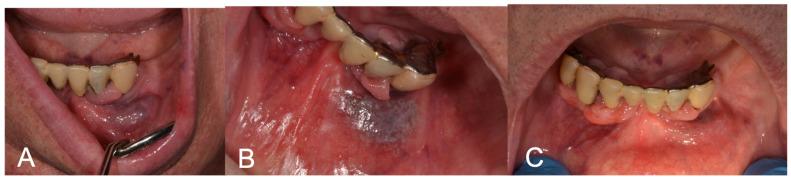

: Low-flow vascular lesions are commonly encountered in the oral cavity and may require removal due to aesthetic concerns, repeated bleeding or a cluttering sensation. Laser devices represent an excellent aid due to their affinity with blood and to their biostimulating properties and have been substituting traditional excision in selected cases. : In this study, 30 patients presenting with low-flow oral vascular lesions were included. The lesions were clinically evaluated as follows: lesion's site, reason for treatment, lesion's dimensions, confirmation of positive diascopy via compression with a glass slide and photograph. The lesions were treated with laser forced dehydration (LFD) and then followed-up after 3 weeks, 6 months and 1 year. The laser source was a K-Laser Blu Derma (Eltech, K-Laser S.r.l., Via Castagnole, 20/H, Treviso, Italy). In the case of incomplete healing, a further protocol was performed at the three-week follow-up, and a further follow-up was scheduled for three weeks after. The following aspects were evaluated at each appointment: pain, using a Numeric Rating Scale (NRS) from 0 to 10 (0 = no pain, 10 = worst pain ever); the need to take painkillers (day of intervention and during follow-up); bleeding (yes/no); scar formation. : Complete regression was obtained in all patients, with no side effects. Only one patient required a second LFD protocol. NRS was 0 for all patients for the whole duration of the follow-up. None of the patients took painkillers on the day of the intervention and during the follow-up. One patient declared slight bleeding the day of the intervention, which she easily managed at home. One patient showed a small non-retracting and non-painful scar at the three-week follow-up. No recurrences were found after six months and one year. : LFD targets endogenous chromophores, minimizing damage to adjacent tissue and limiting side effects. LFD is effective and could be considered a conservative alternative to traditional excision in low-flow lesions.